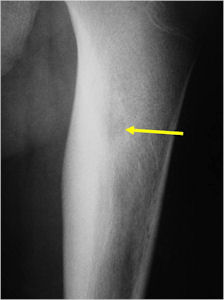

Plain X-Rays:

- Lucent nidus surrounded by a zone of marked sclerosis

- Periosteal bone is solid, rarely lamellated

- Cortical and subperiosteal osteoid osteomas are usually associated with much more reactive sclerosis than medullary tumors

- The periosteal reaction is continuous and often appears as cortical thickening (benign appearing reaction)